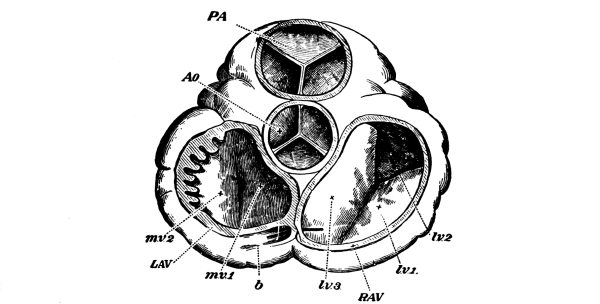

The Heart, 101—The Pericardium, 101—Cavities of the Heart, 103—The Endocardium, 103—The Valves of the Heart, 103—Circulation, 105—Circulation in the Fetus, 106—Arteries, 107—Veins, 109—Portal Circulation, 109—Pulmonary Circulation, 110—Nerves of the Heart, 110—Heart Sounds, 111—The Heart Beat, 111—Factors Affecting Circulation, 112—The Pulse, 113—Blood Pressure, 114—Nerve Supply of the Blood-vessels, 115—The Blood, 116—Composition of the Blood, 116—Coagulability of the Blood, 117—Blood-corpuscles, 118. |